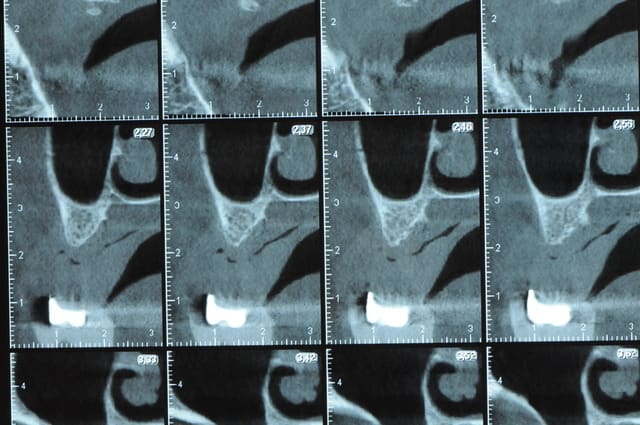

la suite

Une petite étude de ton cas D57

Les zones exploitables radiologiquement parlant:

Coupes implant

2,3 40100

4,96 35130 avec sinus lift mais difficile

5,25 35150

6,02 35130

6,78 35115 après réduction de hauteur de crête

7,26 35115 après réduction de hauteur de crête

8,51 35150

10,43 40115 ou 50115

11,10 40115

Ce qui nous fait 9 implants possible évidement avec un comblement de sinus on augmenterait encore les zones implantable mais ce n’est pas le but recherché, avec 8 (4+4) il doit être possible de faire une belle barre support de complet